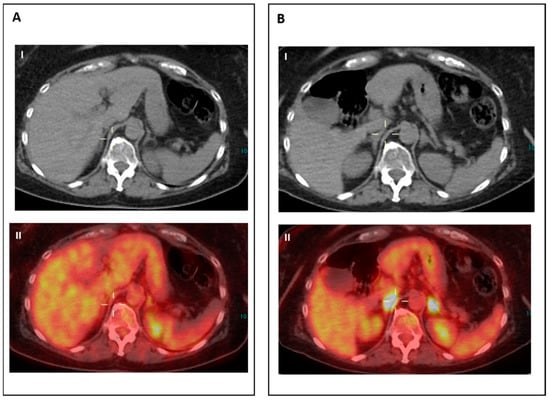

- IR(3): Increase in the uptake of existing lesions without a concomitant increase in lesion size and number (Figure 3).